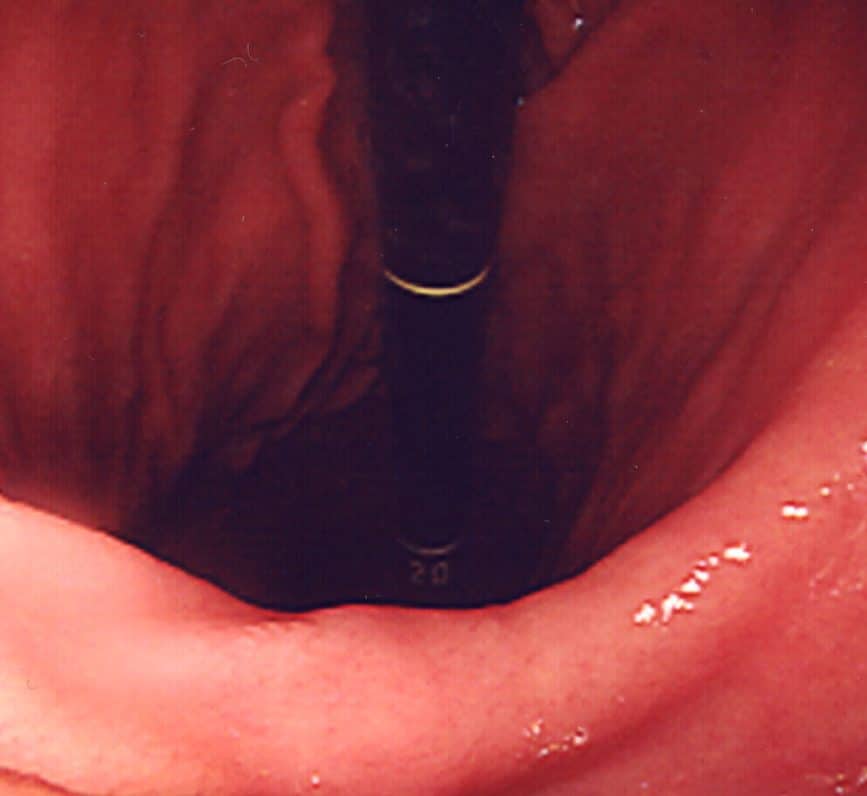

Peptic ulcer disease is the most common cause of melena (Fig. 1). Whilst it can affect any patient group, it should be especially suspected in those with known active peptic ulcer disease, a recent history of NSAID use or steroid use, or known H. pylori infection

Classically, the most significant bleeding will occur if an ulcer erodes through the posterior gastric wall into the gastroduodenal artery. However, in reality, extensive bleeding can occur with the erosion of any blood vessel.

Figure 1 – Endoscopic image of a bleeding gastric ulcer